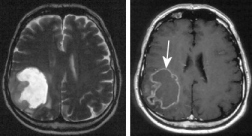

Das

einen grossen Teil der Substanz verloren Das Alzheimerhirn hat gegenüber dem normalen Hirn einen grossen Teil der Substanz verloren. Quecksilber ist wesentlich daran beteiligt.

Die Alzheimer-Krankheit wurde erstmals 1907 vom Breslauer Neurologen Alois Alzheimer beschrieben und tritt bevorzugt bei Frauen zwischen dem 55. und 65. Lebensjahr auf.

Für die überwiegende Zahl aller Fälle eines geistigen Abbaus (Demenz, Einschränkung bzw. Verlust aller Denkprozesse) ist derzeit die Alzheimer-Krankheit verantwortlich. Durchschnittlich tritt der Tod nach 10 Jahren ein (S.41).

Die Ursache ist nach schulmedizinischer Meinung unbekannt; eine früher als Auslöser betrachtete Aluminiumbelastung spielt jedoch eher als Co-Faktor eine Rolle. Etwa 5 % der Alzheimer-Fälle sind genetisch bedingt (Mutationen auf Chromosom 14, 19, 21). Bei der Krankheit lagern sich krankhafte Proteine im Gehirn ab (senile Plaque durch Beta-Amyloid) (S.41).

Verglichen wurden zwei Gruppen. Die eine fasste Menschen zusammen, die an Alzheimer gestorben waren, in der anderen befanden sich alle anderen Patienten. Der Quecksilberspiegel war im Gehirngewebe der Alzheimerpatienten erhöht, und zwar bis zum Vierfachen in Hirnregionen, die bei der Alzheimer-Krankheit degenerieren (S.41).